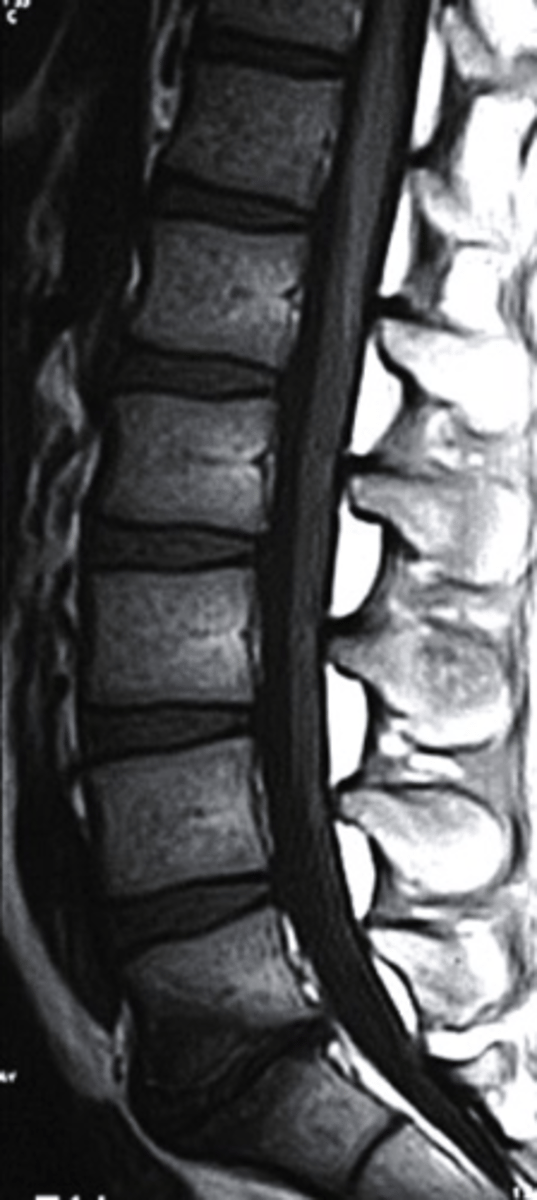

T1 MRI

what type of imaging is this?

a. T2 MRI

b. CT Scan

c. Radiograph

d. T1 MRI